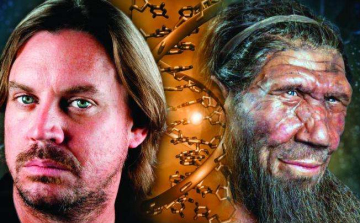

A modern ember betegségeit, magatartását a Neander-völgyi ember DNS-e is befolyásolhatja

A Neander-völgyi embertől örökölt DNS szerepet játszhat a modern ember magatartásában, betegségeiben, növelheti vagy csökkentheti olyan tényezők kialakulásának a kockázatát,